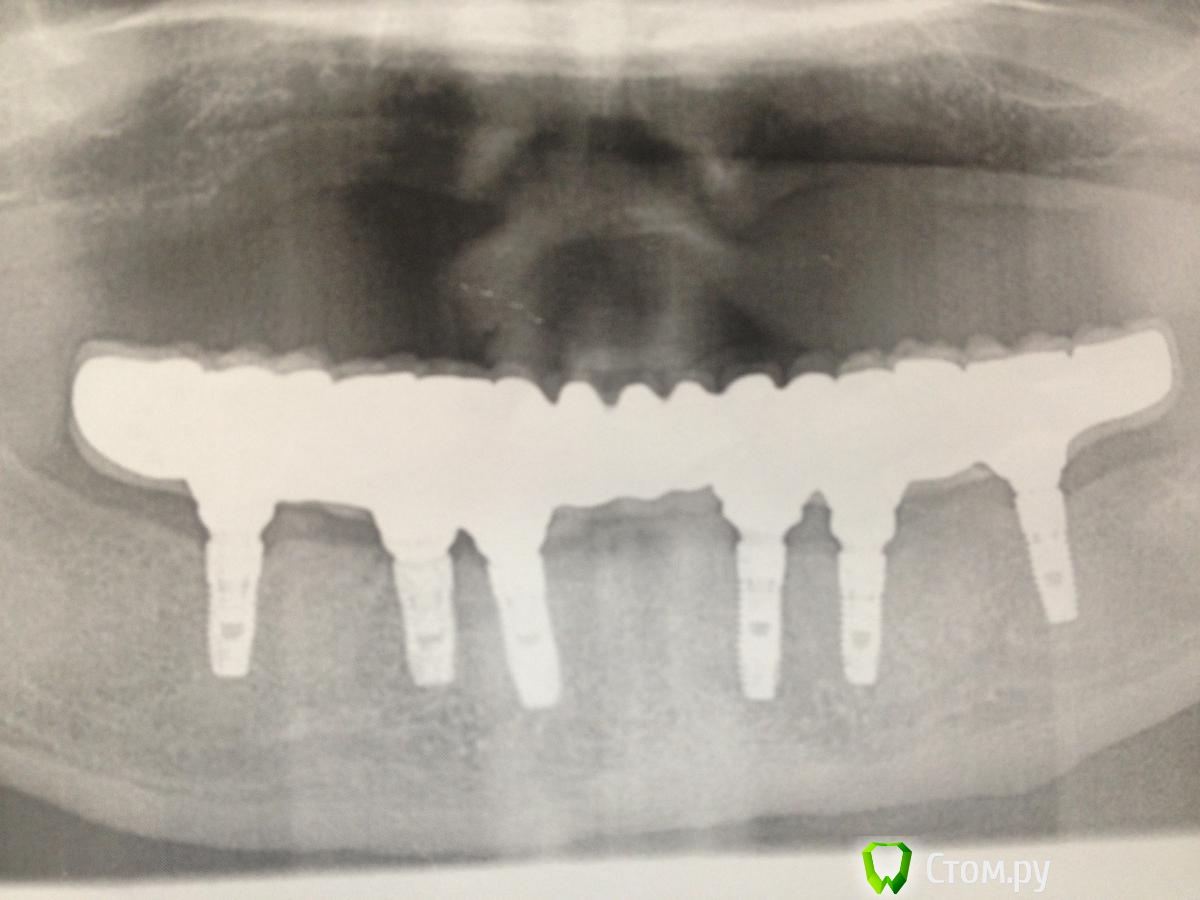

MaxDok Опубликовано 15 февраля, 2014 Поделиться Опубликовано 15 февраля, 2014 (изменено) Интресует правильный ли дизайн промывного пространства ?Критикуйте коллеги. Изменено 15 февраля, 2014 пользователем MaxDok 10 Ссылка на комментарий

MaxDok Опубликовано 15 февраля, 2014 Автор Поделиться Опубликовано 15 февраля, 2014 Красиво! Это цементная фиксация? Каркас литой, а сверху керамика или пластмасса? Спасибо! Цементная,ретракцию везде делал,суперфлоссы во все промежутки в момент цементировки.Каркас изготовлен по технологии лазерного спекания ,облицован керамикой . Ссылка на комментарий

zubovolok Опубликовано 16 февраля, 2014 Поделиться Опубликовано 16 февраля, 2014 Спасибо! Цементная,ретракцию везде делал,суперфлоссы во все промежутки в момент цементировки.Каркас изготовлен по технологии лазерного спекания ,облицован керамикой .какая система имплантов использовалась? Дентиум? Можно по потробней про лазерное спекание? Ссылка на комментарий

MaxDok Опубликовано 17 февраля, 2014 Автор Поделиться Опубликовано 17 февраля, 2014 //////почему решили консольными концами закончить зубной ряд, и что за керамика?, выглядит неплохо)))/////Тут практически везде было расщепление , в области семерок не проходило . А так как передне задний размер конструкции позволяет спать спокойно , то не задумываясь выбрали такой вариант . Керамика Noritake . Спасибо моему зубному технику , старался . Он кстати на форуме тоже иногда появляется . Ссылка на комментарий

MaxDok Опубликовано 17 февраля, 2014 Автор Поделиться Опубликовано 17 февраля, 2014 //// какая система имплантов использовалась? Дентиум? Можно по потробней про лазерное спекание?/// Она самая , что касается технологии изготовлении каркаса ..думаю я не отвечу подробнее чем google )) наберите в поисковике . Ссылка на комментарий